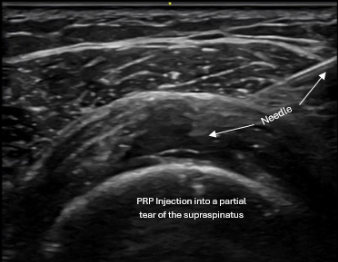

Ultrasound-guided procedures use real-time imaging to precisely visualize the target tissue while a procedure is being performed. This allows the physician to see exactly where the needle is placed, rather than relying on landmarks or feel alone.

Real-time ultrasound guidance showing precise needle placement during procedure